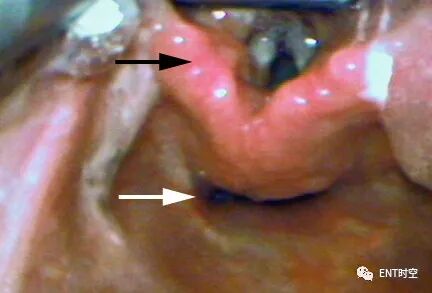

喉镜是怎么麻醉掌握这份喉镜检查秘籍,你也可以是喉镜检查高手!_https://www.jmylbn.com_新闻资讯_第3张

声门和食道的气道观:喉镜检查期间的气道视图。声门具有垂直方向,声带在上方呈白色结构,在后方呈杓状软骨(黑色箭头)。食道呈水平方向,下方呈狭缝状(白色箭头)。